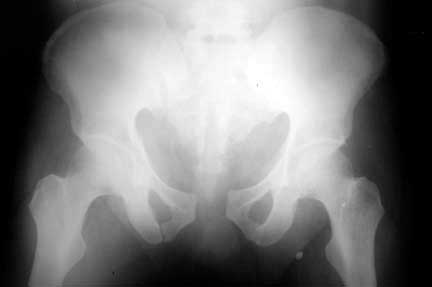

Here are the post op pictures.

To recap: Middle aged male patient on whom a heavy log fell and sustained injury. Had pelvic ring disruption with fracture femur. Ext fix of pelvis and interlocking nailing of femur done. Developed compartment syndrome thigh and had fasciotomy. Went on to rhabdomyolysis and ARDS. Managed with ventillation and alkalinising. Fasciotomy wound later skin grafted.

Now what I have not told so far: At about three weeks after the injury when patient had recovered from the problems described above developed acalculous cholecystitis. As he was being prepared for surgery he suddenely collapsed and went into shock. Required resuscitation and inotropic support. After vital signs were stable he was taken up for laparoscopic cholecystectomy. On introducing the scope it was found that there was a gangrenous gall bladder with lots of inflammation all around. It was converted to an open cholecystectomy. Ventillated post op. Patient's ext fix on pelvis was removed after six weeks and ambulated with walker. Had developed a deep sacral pressure sore. Discharged with home care of pressure sore and ambulation with support. Now at about three weeks the femur is uniting, pelvis stable and the pressure sore healing. Patient changed to axillary crutches from walker.